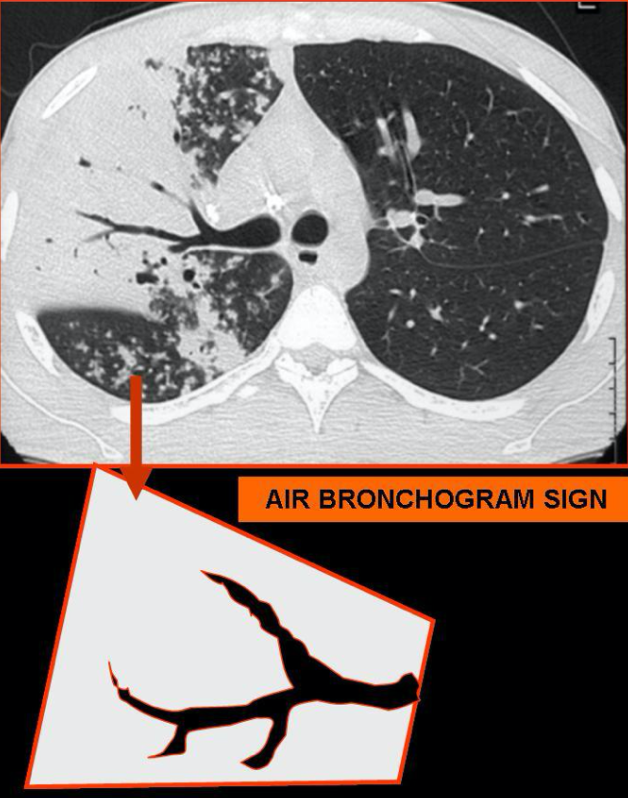

11

Dato clave del patrón de consolidación alveolar

Broncograma aéreo

12

A

Consolidación alveolar